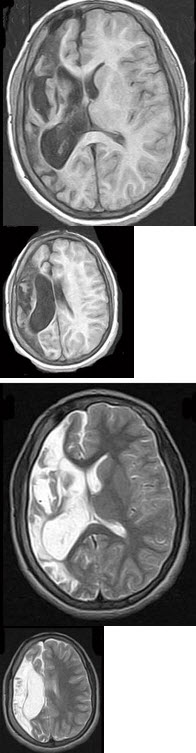

男,35岁,有颅脑外伤史,结合MRI图像选择最可能诊断( )

A:脑软化

B:脑萎缩

C:脑积水

D:脑穿通畸形囊肿

E:脑实质占位